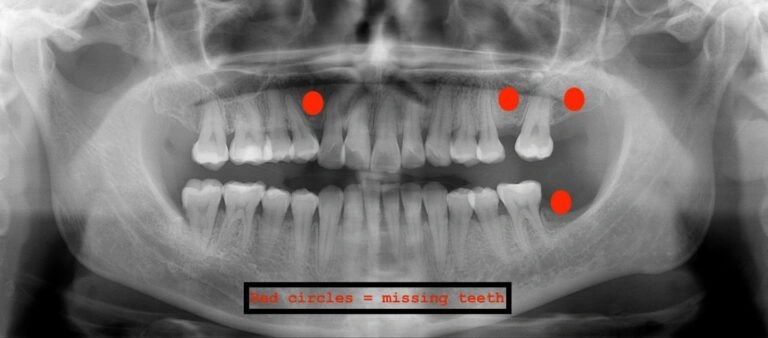

Visual Example:

Example #1 (young adult):

Example #2 (young adult):